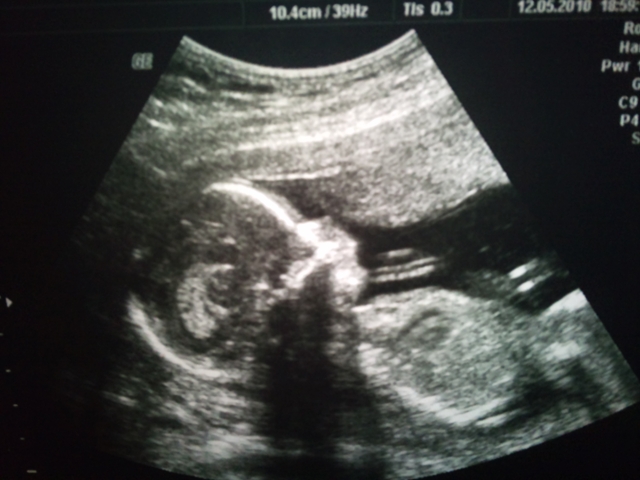

Vi har vært på ultralyd på sykehuset i dag, og alt er perfekt med den lille. I tillegg fikk vi bekreftet at vi får en perfekt liten GUTT!!! 😀 En stolt og rørt tigermamma sitter nå og ser på ultralydbildet av den lille kjekkasen vår, og gleder meg masse til han kommer ut så jeg får klemme og kose på han! *snufs*